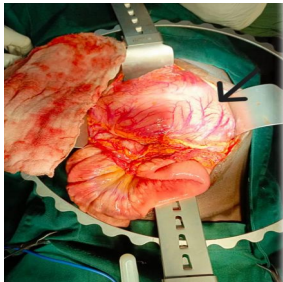

Abdominal Ultrasound: There is an epigastric simple cyst measuring 17x11cm with thickened wall measuring 5.8mm suggesting pancreatic pseudocyst.

Figure 1